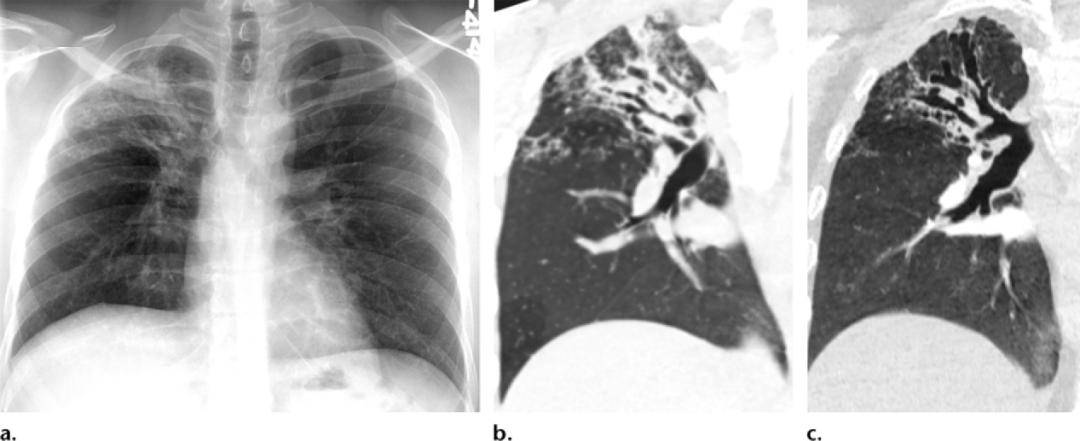

(a)后前位x线显示平行分布的分支线状影(轨道征),代表支气管扩张.